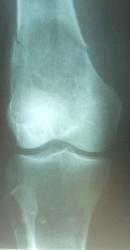

Патологический перелом дистального метафиза бедра, в котором определяется большой участок деструкции многокамерной структуры, занимающий весь поперечник кости, окаймленный ободком склероза, слегка вздувающий кость. Кортикальный слой резко истончен. Остеопороз в проксимальном эпиметафизе б/берцовой кости. Склоняюсь к костной кисте. Через 2 года на месте перелома динамика развития склеротических изменений (тенденция к самоизлечению кисты? хотя не могу исключить замещение ткани кисты трансплантатом, т.е. оперативное вмешат-во), уменьшение выраженности остеопороза в проксим. эпиметафизе б/берцовой кости.

Перелом патологический, на фоне очага литической деструкции. Возможно, ГКО. Может быть аневризмальная киста, хондрома. Какое лечение? - Ну, наверное, удаление образования и костная пластика, не знаю. А может самоизлечение?

1.Вероятнее гигантоклеточная опухоль, патологический перелом.

2. Предположительно - лечение оперативное, ревизия полости дструкции с дальнейшим пломбированием.

Представлен случай гиперпаратиреоидной остеодистрофии. А лечение соответственно - удаление аденомы паращитовидной железы. На кости операций не было.